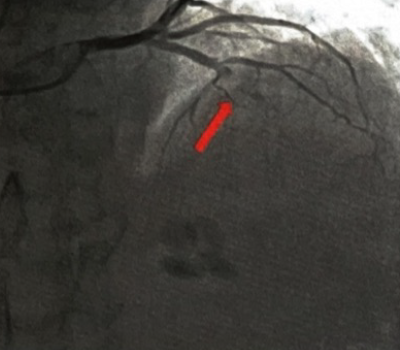

◇现病史:患者9年前某日突发胸痛不适,症状持续不缓解,急至我院行相关检查后诊断为“急性广泛前壁心肌梗死",急诊冠状动脉造影示前降支(LAD)中段狭窄95%,回旋支及右冠状动脉(RCA)未见狭窄,于LAD置入1枚药物洗脱支架。出院后坚持规律服药,未再发作胸痛不适。3年前至我院门诊常规复诊,心脏超声检查发现心尖部室壁瘤并血栓形成,予以华法林治疗。后患者逐渐出现活动后胸闷感、喘气不适,伴乏力、夜间阵发性呼吸困难及端坐呼吸。2年前症状加重再次至我院住院治疗,行冠状动脉造影检查提示:RCA未见狭窄,LAD近段完全闭塞(图1),介入开通闭塞病变后,在LAD支架远段置入1枚药物洗脱支架,与原支架部分衔接,术后积极行药物治疗,仍间断于活动后出现喘气不适,伴乏力、夜间阵发性呼吸困难,曾多次至我院住院调整心功能。

图1. 冠状动脉造影(2020年):前降支中段原支架中远段闭塞,闭塞处可见血栓影(箭头所示)